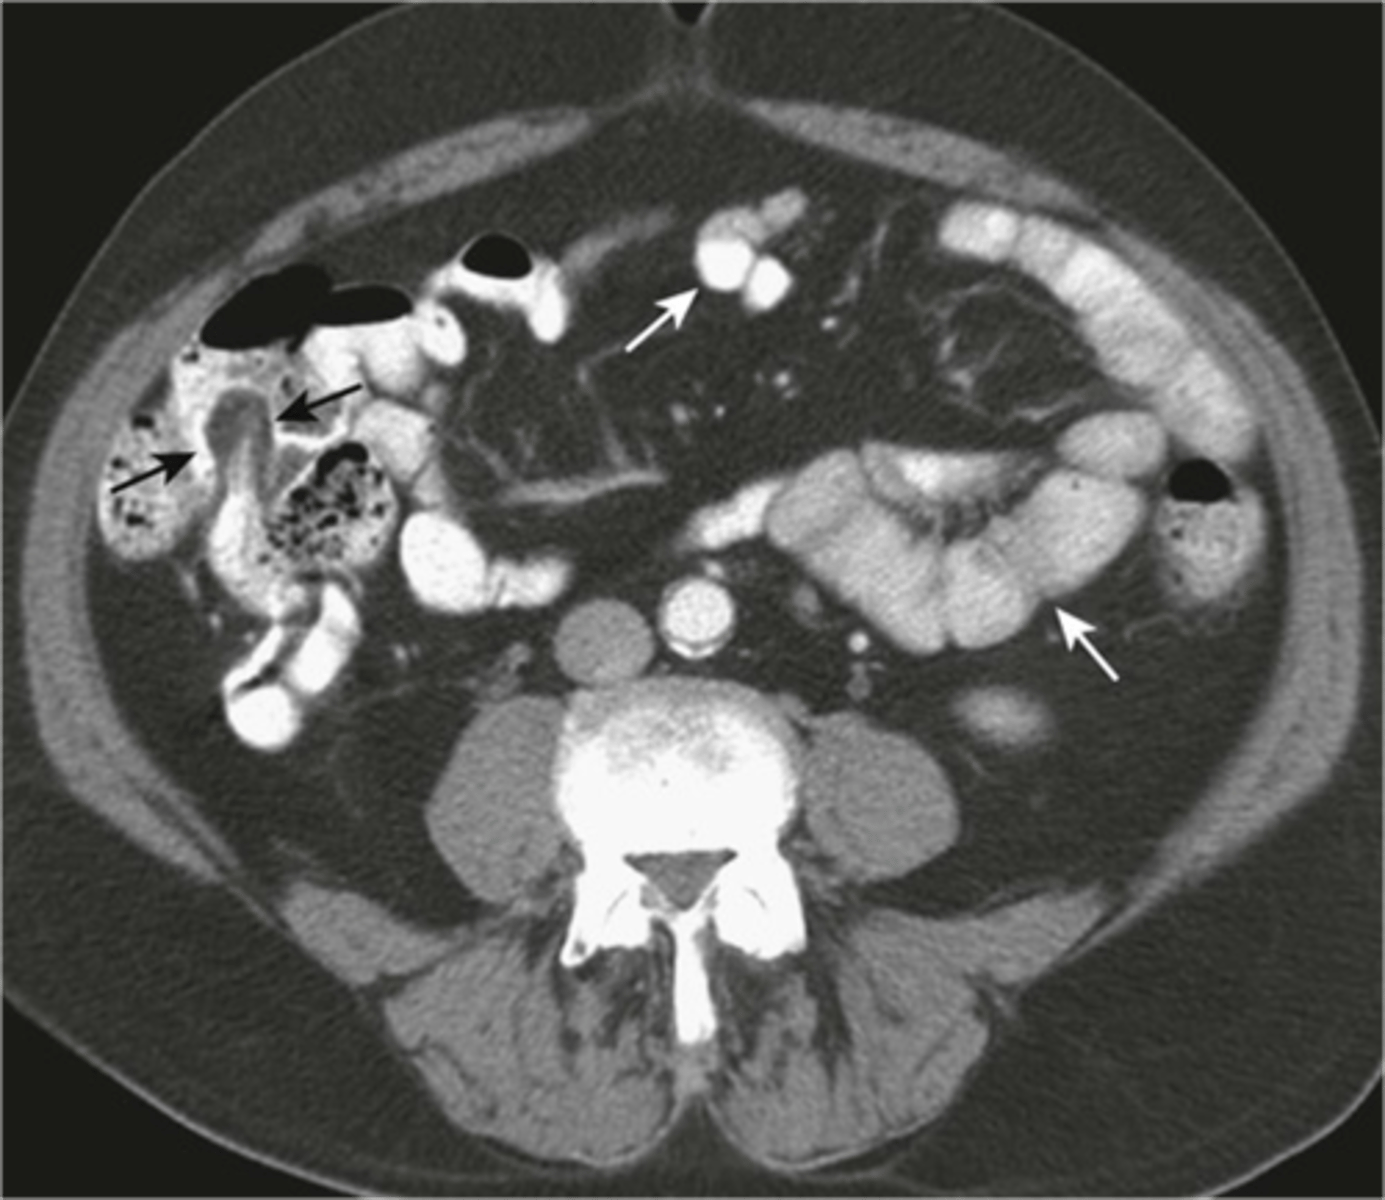

Normal small and large bowel on CT